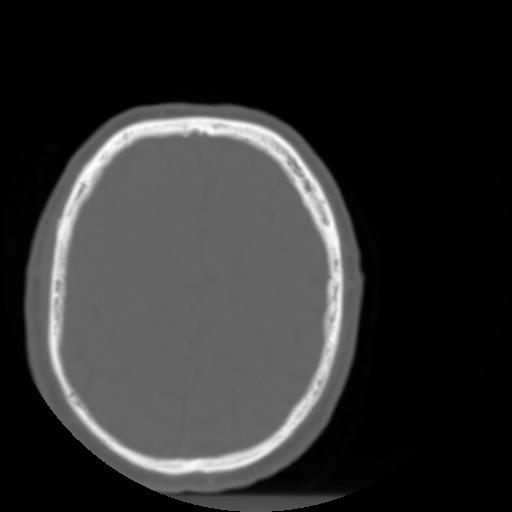

3 CEREBRO,,Axial,3.0,CEREBRO,,